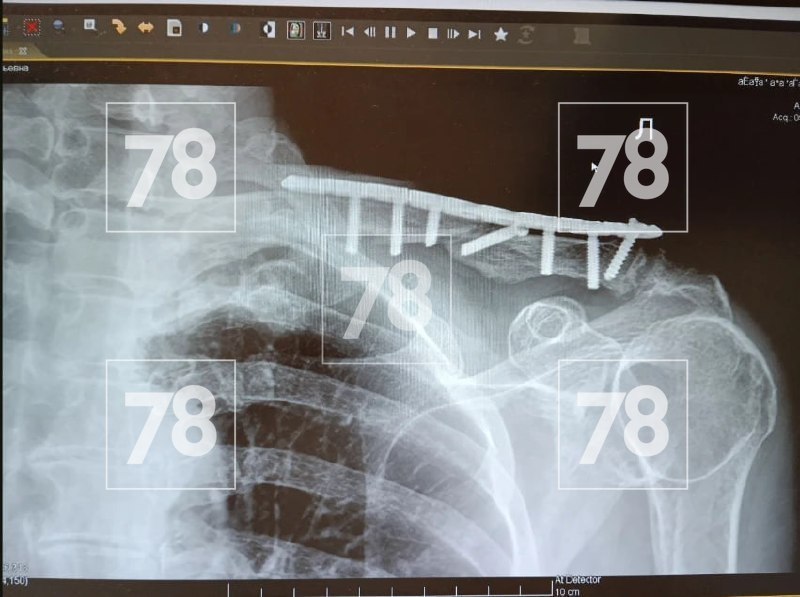

«Они накинулись на нас. Сначала она с баллончиком, потом он с палкой. В итоге у мамы перелом ключицы и ожог роговицы»,

— поделилась Евгения.

Мать девушки уже прооперировали, она находится на реабилитации. Был серьёзный перелом ключицы со смещением и сотрясение мозга. Семья обратилась в прокуратуру.